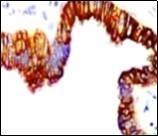

Alternatively, cutaneous ciliated cyst can be lined by non ciliated cuboidal or columnar epithelium with intermingled intercalated, dark or round peg cells. Foci of squamous metaplasia can be occasionally exemplified in the adherent epithelium whereas mucinous cells or apocrine-like features are exceptional 6, 8. Figure 1, Figure 2, Figure 3, Figure 4, Figure 5, Figure 6, Figure 7, Figure 8, Figure 9, Figure 10, Figure 11, Figure 12. 11, 12, 13, 14, 15, 16, 17, 18, 19.

Figure 12.Cutaneous ciliated cyst with nuclear immune reactivity to oestrogen receptors (19).

Epithelium of cutaneous ciliated cyst is immune reactive for pan cytokeratin (CKae1/ae3) antigens, epithelial membrane antigen (EMA), oestrogen receptors (ER), progesterone receptors (PR), Wilm’s tumour protein (WT-1) and paired box gene 8 (PAX8). Immune non reactivity is cogitated for S100, smooth muscle actin (SMA), carcino-embryonic antigen (CEA), desmin, thyroid transcription factor(TTF1), p63 and glial fibrillary acidic protein (GFAP).

Smooth muscle actin (SMA) is immune non reactive, thereby suggesting an absence of smooth muscle within the cyst wall. Intense immune reactivity can be cogitated within epithelial nuclei for oestrogen receptors (ER) and progesterone receptors (PR). Aforesaid immune reactions are indicative of Mullerian origin of cutaneous ciliated cyst.

Cutaneous ciliated cyst demonstrates immune reactivity to Dyein, akin to the reaction elicited in normal fallopian epithelium. Nevertheless, atypical locations of cutaneous ciliated cyst or those arising in males are immune non- reactive with oestrogen receptors (ER) and progesterone receptors (PR) on account of enunciated eccrine glandular epithelium. However, particular instances are immune reactive with carcinoembryonic antigen (CEA), p63, S100 and gross cystic fluid disease protein (GCFDP-15) 8, 9.